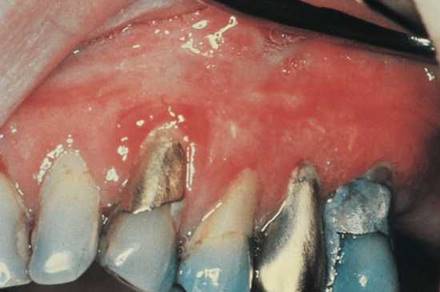

Normal gingivae are stippled, pink, and firm. Does the gingival tissue completely occupy the interdental space? Are the roots of the teeth visible, indicating recession of the periodontal tissue? Is there pus or blood along the gingival margin? Are the gingivae swollen? Is there evidence of bleeding? Is gingival inflammation present? Is abnormal coloration present? Erythroplakia is an area of mucous membrane on which there are granular, erythematous papules that bleed. Erythroplakia has a greater potential for malignancy than does leukoplakia. Figure 12-20 shows the mouth of a patient with erythroplakia of the gingiva (on the right) and inflammatory gingivitis (on the left).

Figure 12-20 Erythroplakia of the gingiva (right).